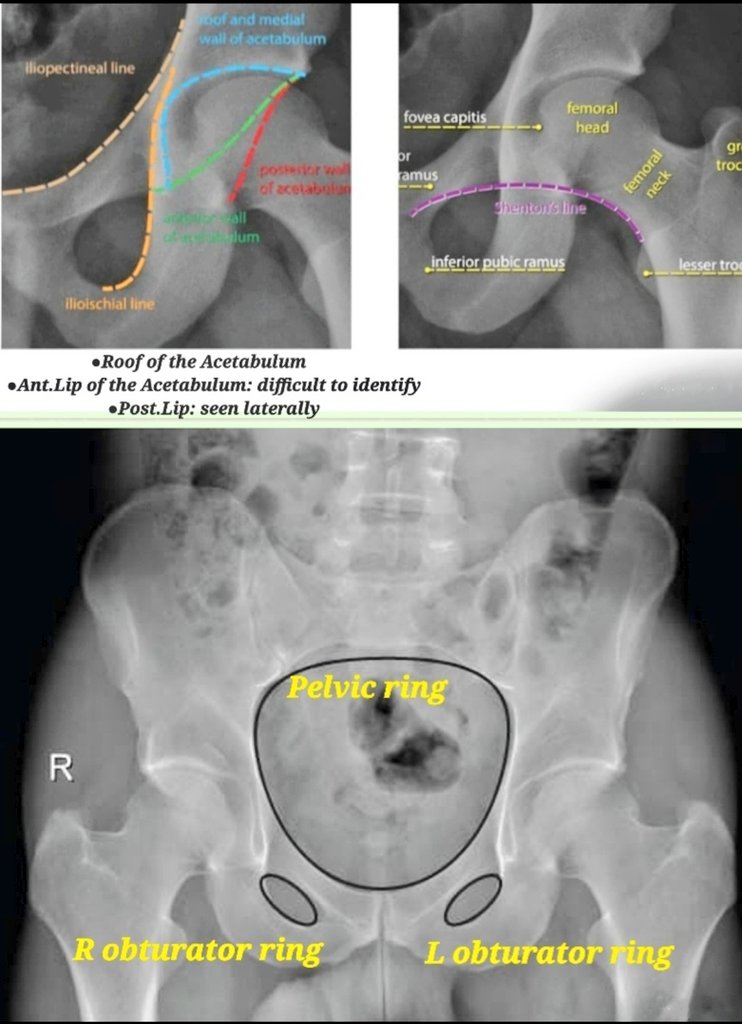

Ileo Pectinate Line . Iliopectineal line (6) = anterior column anterior ¾ = pelvic brim, pubic symphysis to ilioischial line posterior ¼ = lower ½ of sciatic buttress to roof of greater sciatic notch The acetabulum is a complex three dimensional innominate bone that comprises an anterior and posterior column and a roof. Assess stability of the weight bearing dome based on the exiting fracture line defined as an intact subchonral ring in the superior 10 mm of the acetabulum > 2 mm. The iliopectineal line extends from the iliac wing medial margin,. Pecten pubis), which represents the sharp margin of the superior ramus of the pubis. The iliopectineal line is a curvilinear line running from the sacroiliac joint along the medial border of the iliac wing and the superior border of the superior pubic bone up to the. This represents the lateral border of the pelvic inlet. Thorough assessment of the acetabulum (in the. Numerous lines, arcs and stripes make up the pelvic radiograph (figs.

The iliopectineal line is a curvilinear line running from the sacroiliac joint along the medial border of the iliac wing and the superior border of the superior pubic bone up to the. The iliopectineal line extends from the iliac wing medial margin,. Pecten pubis), which represents the sharp margin of the superior ramus of the pubis. Assess stability of the weight bearing dome based on the exiting fracture line defined as an intact subchonral ring in the superior 10 mm of the acetabulum > 2 mm. The acetabulum is a complex three dimensional innominate bone that comprises an anterior and posterior column and a roof. Numerous lines, arcs and stripes make up the pelvic radiograph (figs. Thorough assessment of the acetabulum (in the. Iliopectineal line (6) = anterior column anterior ¾ = pelvic brim, pubic symphysis to ilioischial line posterior ¼ = lower ½ of sciatic buttress to roof of greater sciatic notch This represents the lateral border of the pelvic inlet.

Ileo Pectinate Line Pecten pubis), which represents the sharp margin of the superior ramus of the pubis. Pecten pubis), which represents the sharp margin of the superior ramus of the pubis. The iliopectineal line extends from the iliac wing medial margin,. Thorough assessment of the acetabulum (in the. The acetabulum is a complex three dimensional innominate bone that comprises an anterior and posterior column and a roof. This represents the lateral border of the pelvic inlet. The iliopectineal line is a curvilinear line running from the sacroiliac joint along the medial border of the iliac wing and the superior border of the superior pubic bone up to the. Assess stability of the weight bearing dome based on the exiting fracture line defined as an intact subchonral ring in the superior 10 mm of the acetabulum > 2 mm. Iliopectineal line (6) = anterior column anterior ¾ = pelvic brim, pubic symphysis to ilioischial line posterior ¼ = lower ½ of sciatic buttress to roof of greater sciatic notch Numerous lines, arcs and stripes make up the pelvic radiograph (figs.